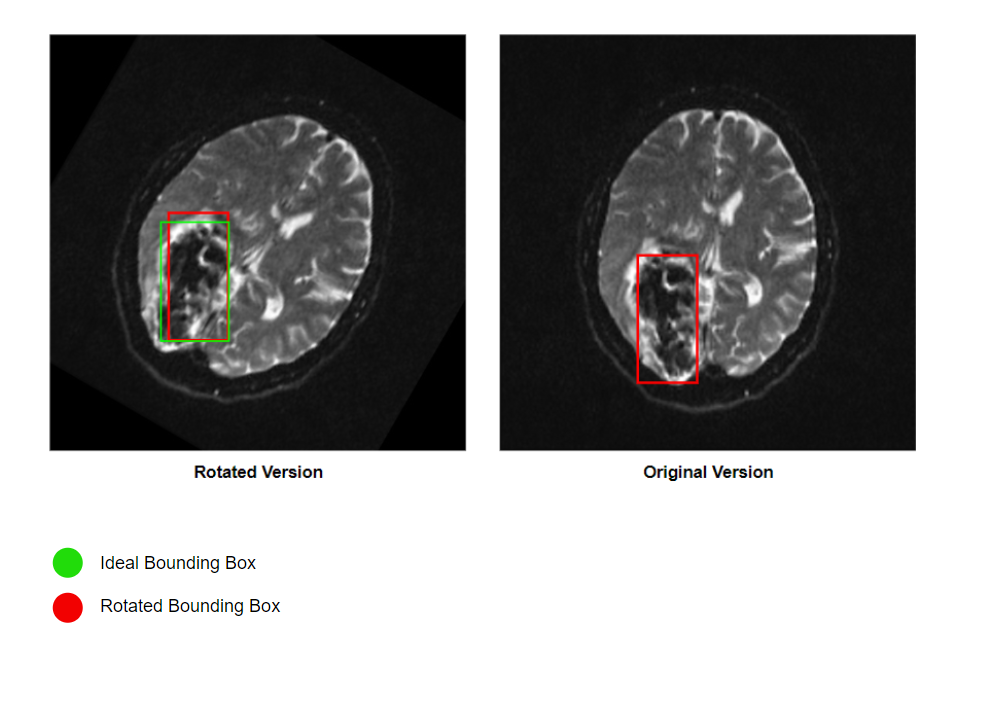

In first training attempt we ended up with a precise model with low recall score as we were inducing unwanted misinformation into the model’s learning path. The bounding boxes that we specified for tumor regions were accurate in the majority of the augmentations including the vertical and horizontal flips.

Refer to caption

Figure 7: The rotation of bounding boxes has a notable impact on our models, affecting their ability to accurately outline objects by introducing misleading information within the boxed area. The extent of this inaccuracy depends on the tumor’s shape, size, and how much it is rotated.

However, the rotation of the image and the corresponding object of interest (Tumor) was injecting false information into the Tumor class. This happened when we attempted to rotate the bounding box around its initial center using our custom module, and some non-tumor regions were injected in the new bounding box region. Therefore, we decided to stay with more reliable augmentation effects such as vertical, horizontal flips and brightness intensity.